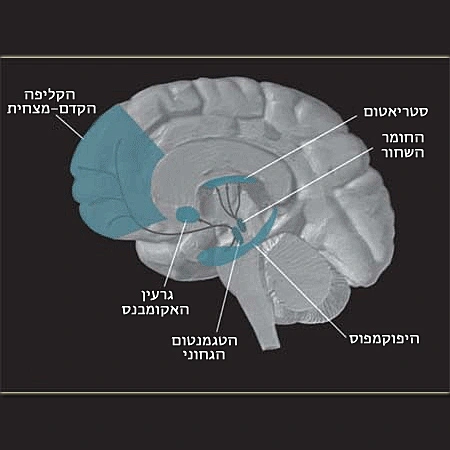

הבדיקה של החוקרים העלתה תגלית מפתיעה: מסתבר כי באותם הרגעים של התגלות משיחית אלוהית, נרשם זינוק בפעילות המוחית שנמדדה באזור במח המכונה "קליפת המוח הקדם-מצחית", אזור שמיוחסת לו חשיבות בכל הקשור ליכולות חברתיות תקשורתיות ובניהם זכרונות ורגשות. במאמר המדעי שפרסמו תחת הכותרת "אלוהים שלח אותי אליכם" מספרים החוקרים כי ההזיה המשיחית הדתית היתה ככול הנראה תוצאה של התקף פסיכוטי שהתרחש לאחר התקף אפילפטי שעבר המטופל. למרות המדידות, אין להם מושג מדוע דווקא בחלק הזה של המח נרשם זינוק בפעילות בזמן החוויה הדתית שהמטופל עבר.